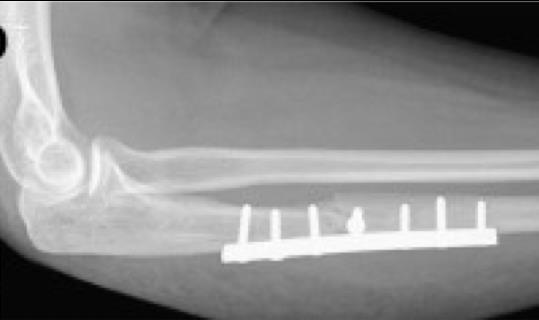

A 45-year-old male presents to the ED after sustaining a fall while mountain biking. His injury films are shown in Figure A. Subsequent imaging obtained immediately after ulnar fixation are shown in Figure B. Which of the following should be performed next?

The radiocapitellar joint is dislocated following fixation of the ulnar fracture. In this situation, the surgeon should revise and re-reduce the ulna fracture.

Monteggia fractures consist of a proximal ulna fracture with a concomitant radial head dislocation. The direction of radial head dislocation classically follows the apex of the ulna fracture, which is the premise of the Bado Classification. These injuries require open reduction internal fixation (ORIF) to provide a stable elbow. Following fixation of the ulna, the elbow should be flexed and the stability of the radial head evaluated. If the radial head is not found to be stable the ulna is malreduced and requires revision ORIF.

Figure A is the injury film demonstrating a Bado I Monteggia fracture. Figure B is the immediate postoperative image showing persistent dislocation of the radiocapitellar joint. Illustration A is a radiograph following revision ORIF of the ulna and subsequent reduction of the radial head.